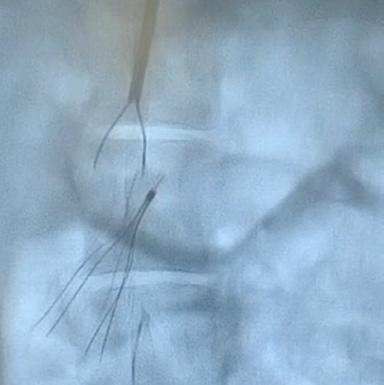

Deep venous arterialization (DVA) was performed using the Pioneer Plus catheter for IVUS-guided arterial re-entry (see Figure 1). Visualization of the popliteal artery re-entry target by IVUS allowed for rapid crossing from the posterior tibial venous access site (see Figure 2).

For those that qualify for intervention based on currently used criteria, vascular access is obtained in the standard fashion with ultrasound guidance. Caval venography is performed to ensure no anatomic abnormality, thrombosis or clot in transit. The right heart is then catheterized—I am a fan of the angled pigtail more so than a balloon-tipped catheter such as the Swan-Ganz as I feel its shape mirrors the anticipated trajectory. For each one of my PE interventions, a full right heart catheterization is performed. A comfort with waveform analysis traversing right atrium, right ventricle and into the main pulmonary artery is paramount. These are standard displays in a cardiac catheterization laboratory, although not usual in the operating suite, so depending on your site of care, it is important to equip your lab with the ability to transmit and display these data. Clearly this